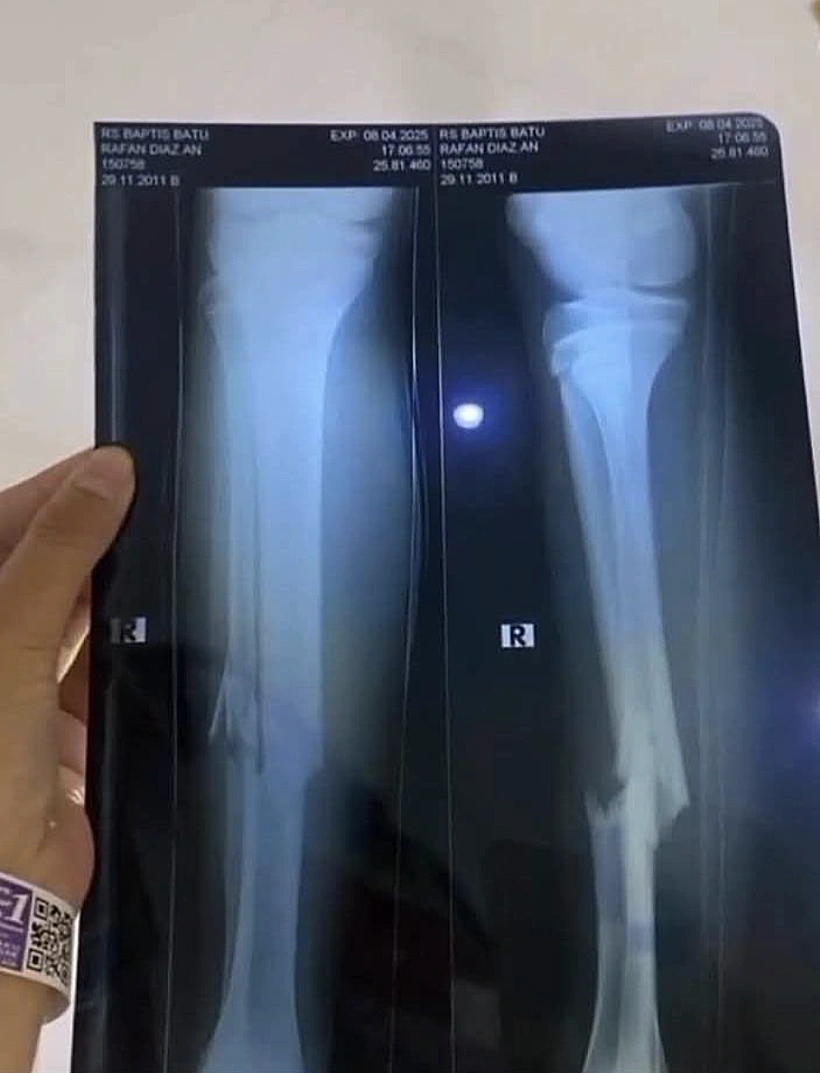

נער בן 13 מאינדונזיה נפל מהמתקן שעמד במהופך באוויר - ונפצע קשה. הוא פונה לבית החולים עם שלושה שברים

על פי הדיווחים, הנער נפל מגובה של כ-2 מטרים ונחבל קשות. הוא פונה לבית חולים עם שני שברים בידו הימנית ושבר נוסף ברגלו.